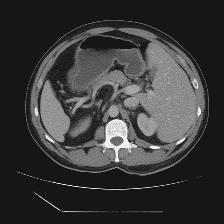

Medical image segmentation is one of the most fundamental tasks concerning medical information analysis. Various solutions have been proposed so far, including many deep learning-based techniques, such as U-Net, FC-DenseNet, etc. However, high-precision medical image segmentation remains a highly challenging task due to the existence of inherent magnification and distortion in medical images as well as the presence of lesions with similar density to normal tissues. In this paper, we propose TFCNs (Transformers for Fully Convolutional denseNets) to tackle the problem by introducing ResLinear-Transformer (RL-Transformer) and Convolutional Linear Attention Block (CLAB) to FC-DenseNet. TFCNs is not only able to utilize more latent information from the CT images for feature extraction, but also can capture and disseminate semantic features and filter non-semantic features more effectively through the CLAB module. Our experimental results show that TFCNs can achieve state-of-the-art performance with dice scores of 83.72\% on the Synapse dataset. In addition, we evaluate the robustness of TFCNs for lesion area effects on the COVID-19 public datasets. The Python code will be made publicly available on https://github.com/HUANGLIZI/TFCNs.

翻译:医学图像分解是医学信息分析的最根本任务之一,到目前为止已经提出了各种解决办法,包括许多深层次的学习技术,如U-Net、FC-DenseNet等。 然而,高精度医学图像分解由于医疗图像中存在固有的放大和扭曲,以及存在与正常组织密度相似的损伤,因此仍是一项极具挑战性的任务。在本文件中,我们建议TFCN(全面革命稠密网络的传输者)通过向FC-DenseNet引进ResLear-Transerferent(R-Transerfor)和Culvacial线性关注区(CLAB)来解决这一问题。TFCN不仅能够利用CT图像中更多的潜在信息来提取特征,而且还能够通过CLAB模块更有效地捕捉和传播语性特征和过滤非神经性特征。我们的实验结果表明,TFCN可以在Syapseion/SymblyDDS上以83CN-72 ⁇ 的分数实现状态。此外,我们在Synapse-DRIS数据设置上,我们还将评估CUTFTFI/LIS的可靠度。